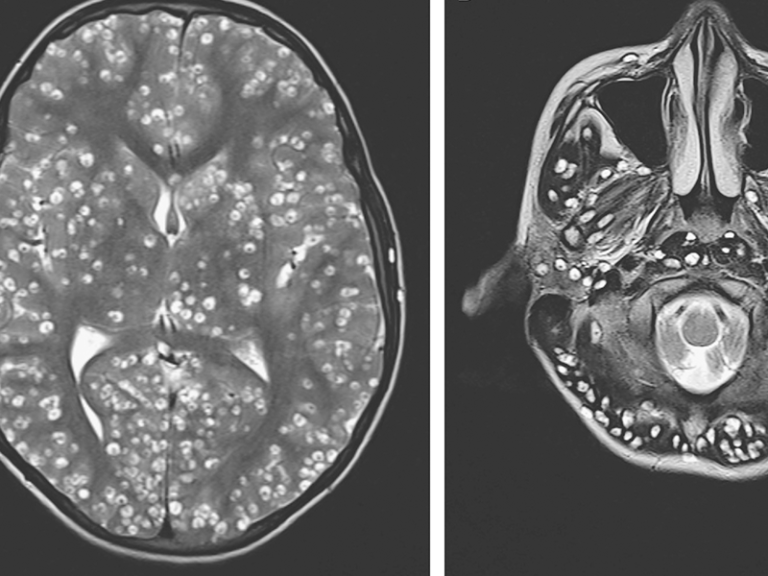

Inmediatamente le realizaron una resonancia magnética y exámenes de ultrasonido, detectaron que en la corteza cerebral y el tronco encefálico el joven albergaba larvas, provocadas por un parásito porcino.

La enfermedad diagnosticada por los médicos fue neurocisticercosis, que ataca inmediatamente al cerebro.

Según la Organización Mundial de la Salud (OMS), esta enfermedad afecta el sistema nervioso y los seres humanos la contraen después de consumir alimentos poco cocinados, especialmente de cerdo, si consumen agua contaminada con huevos de tenia (que ha entrado en contacto con excrementos de alguien que tenía la infección) o por prácticas de higiene deficientes.